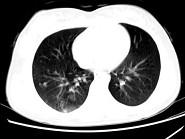

问题 女,24岁,HCG阳性,咯血2天,行胸部CT扫描如图,其最可能的诊断为 ( )

选项 A.转移性绒癌 B.肺部感染 C.肺结核 D.肺血管瘤 E.肺淋巴管肌瘤

答案 A